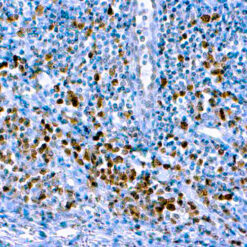

CD79a Antigen (HM47/A9)

This antibody is specific to human CD79a antigen complex, consisting of two polypeptides non-covalently associated with membrane-bound immunoglobulins on B cells. This complex of polypeptide and immunoglobulins constitute the B cell antigen receptor. The two components of this complex are designated CD79a and CD79b. The CD79a antigen appears at the pre-B cell stage, early in maturation and persists until the plasma cell stage. The CD79a antigen is found in majority of acute leukemias of precursor B cell type, in B cell lines and B cell lymphomas.

| Positive Control Tissue | Tonsil |